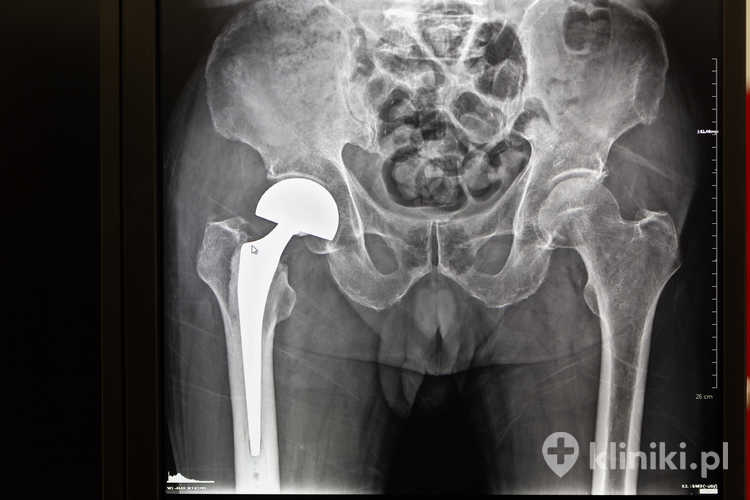

Kiedy leczenie zachowawcze stawu biodrowego przestaje być wystarczające, należy rozważyć przeprowadzenie zabiegu całkowitej alloplastyki stawu biodrowego, podczas którego zniszczony staw biodrowy jest zastępowany sztucznym, czyli endoprotezą. Endoprotezy cementowe są osadzane w kości za pomocą specjalnego, obojętnego dla tkanek cementu kostnego. Endoprotezy te stosuje się zazwyczaj u osób starszych, u których tkanka kostna jest słabsza, a jej gojenie przebiega dłużej.

Podczas zabiegu całkowitej alloplastyki stawu biodrowego zużytą głowę kości udowej zastępuje się metalową lub ceramiczną kulą, osadzoną na trzpieniu, podczas gdy panewka zostaje rozwiercona i zastąpiona plastikową lub metalową wkładką. Endoproteza cementowa mocowana jest do kości za pomocą cementu kostnego (stąd nazwa tego typu implantu).

Jest to metylometakrylan, który w egzotermicznym procesie polimeryzacji zastyga i zapewnia mocne połączenie elementów endoprotezy z kością.